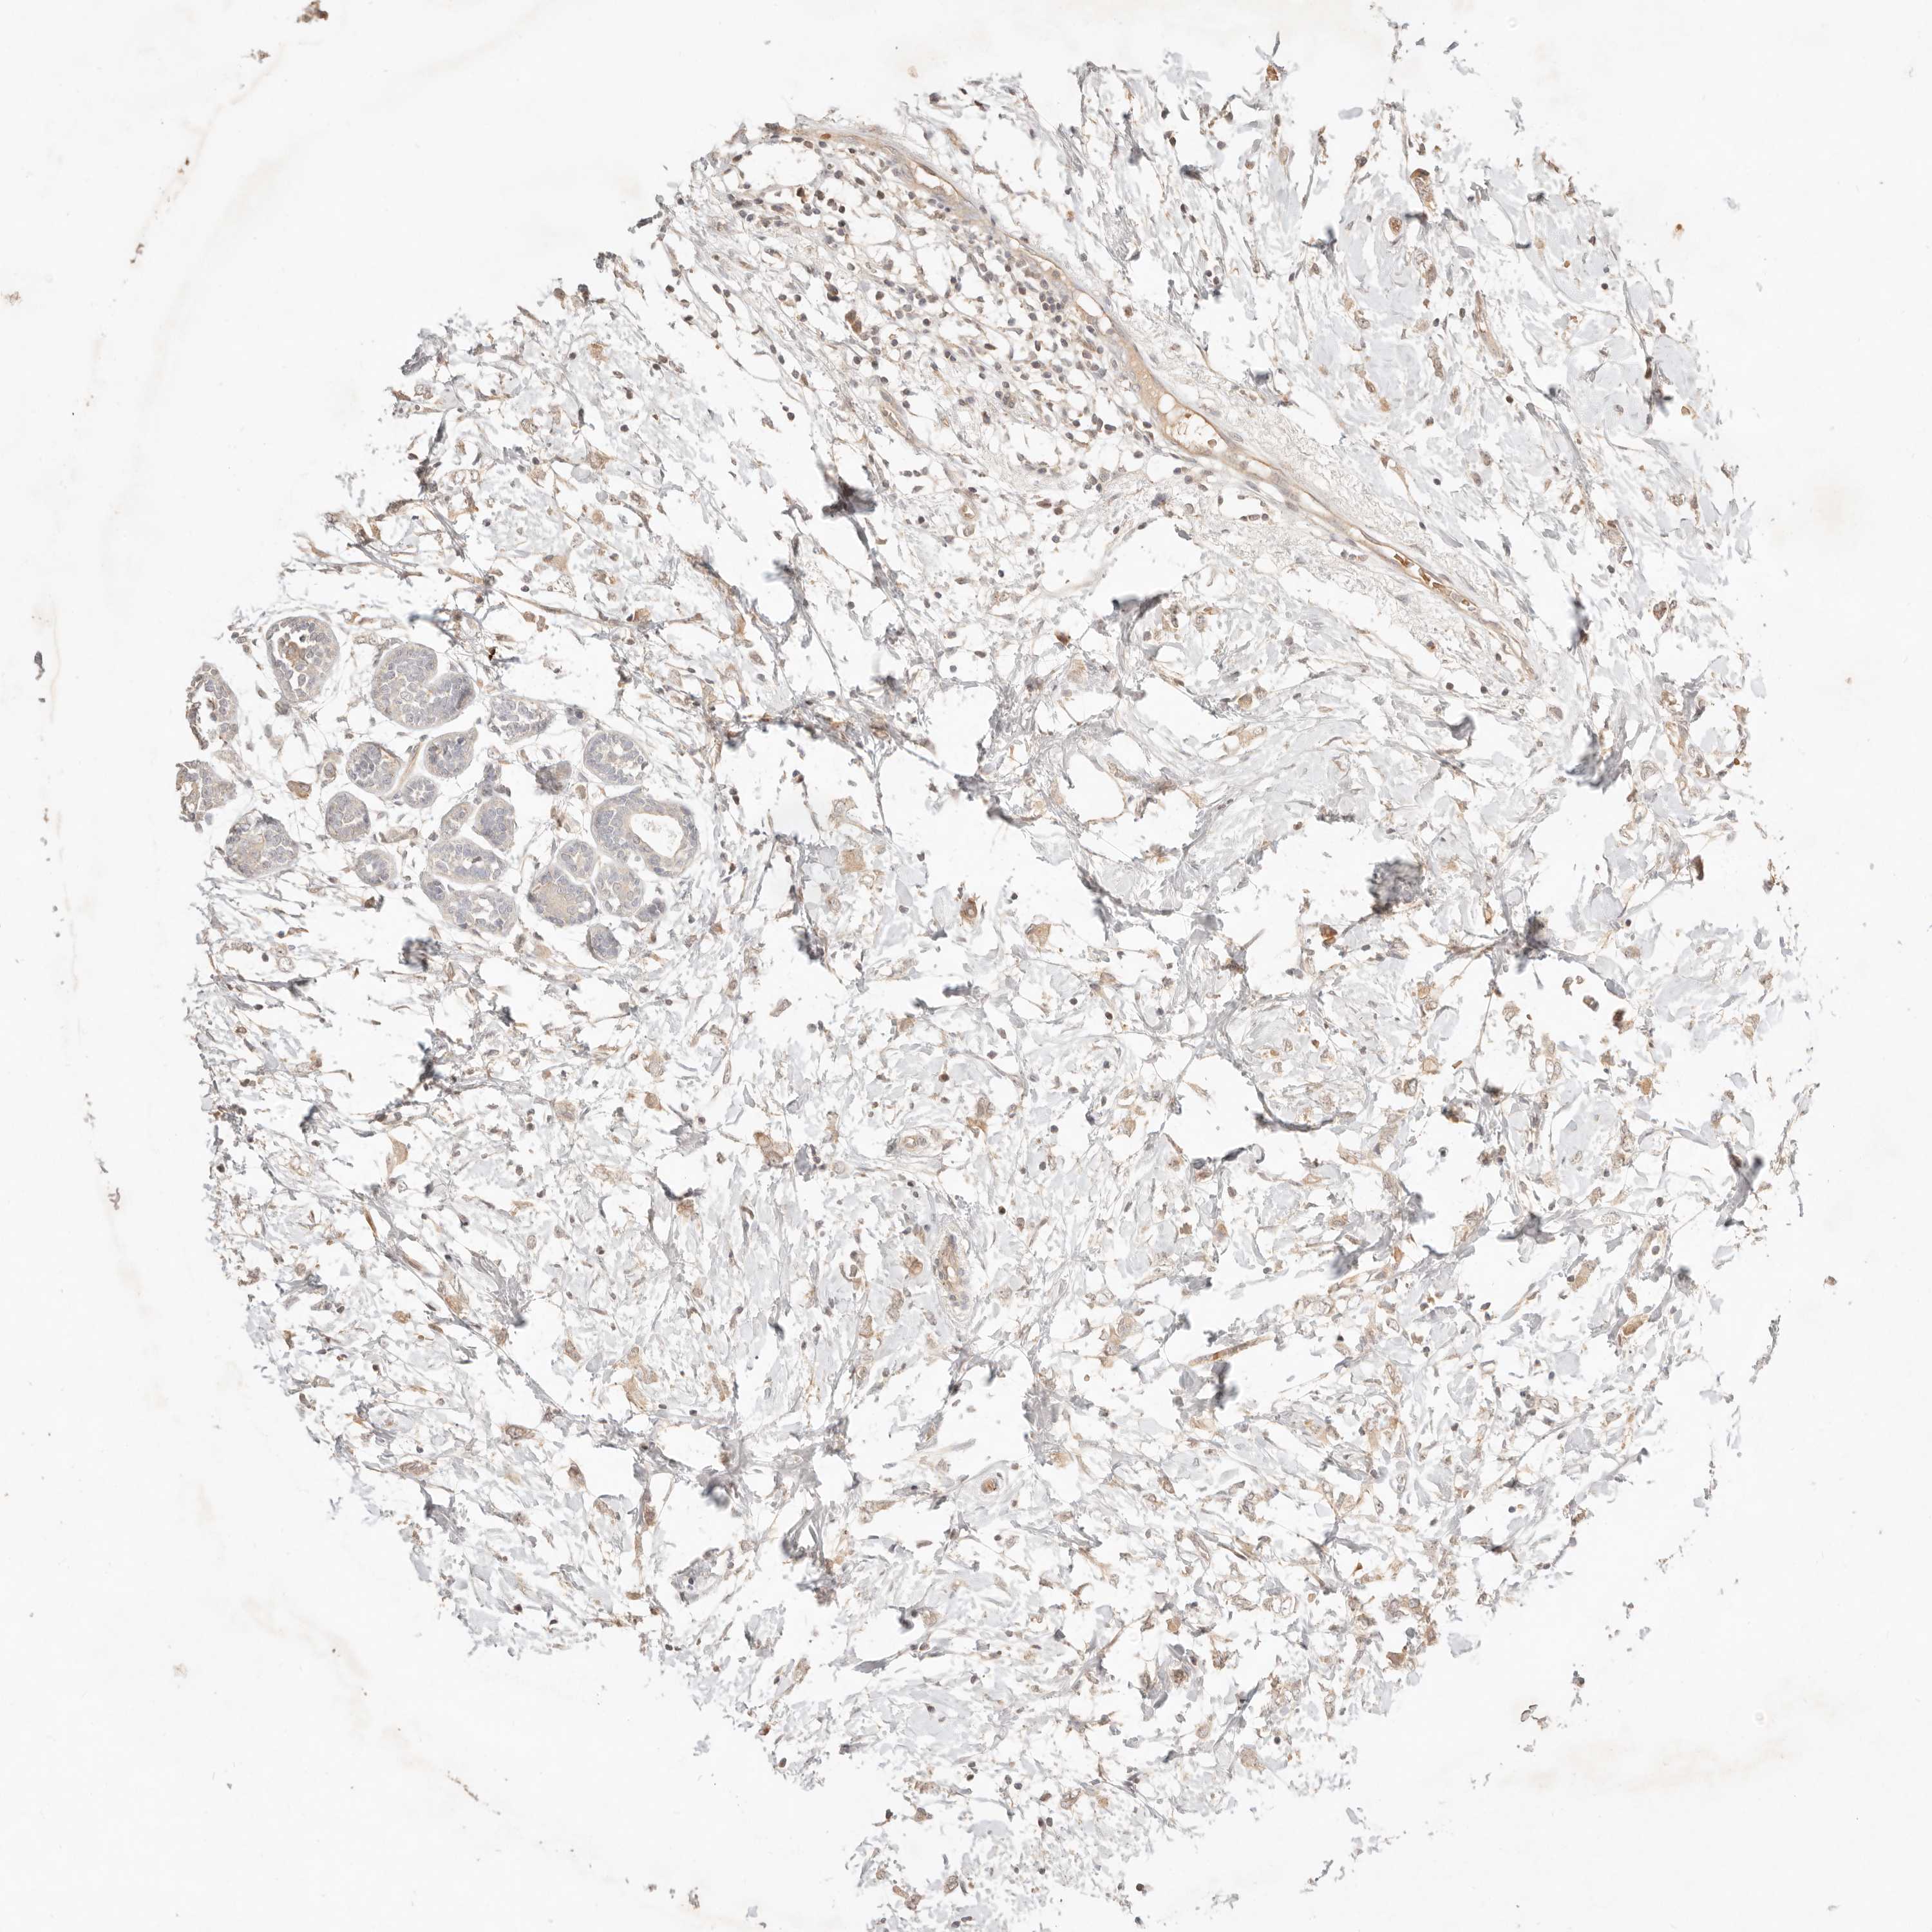

CANCER BREAST CANCER Show tissue menu

BRCA TCGA BRCA VALIDATION PROTEIN EXPRESSION